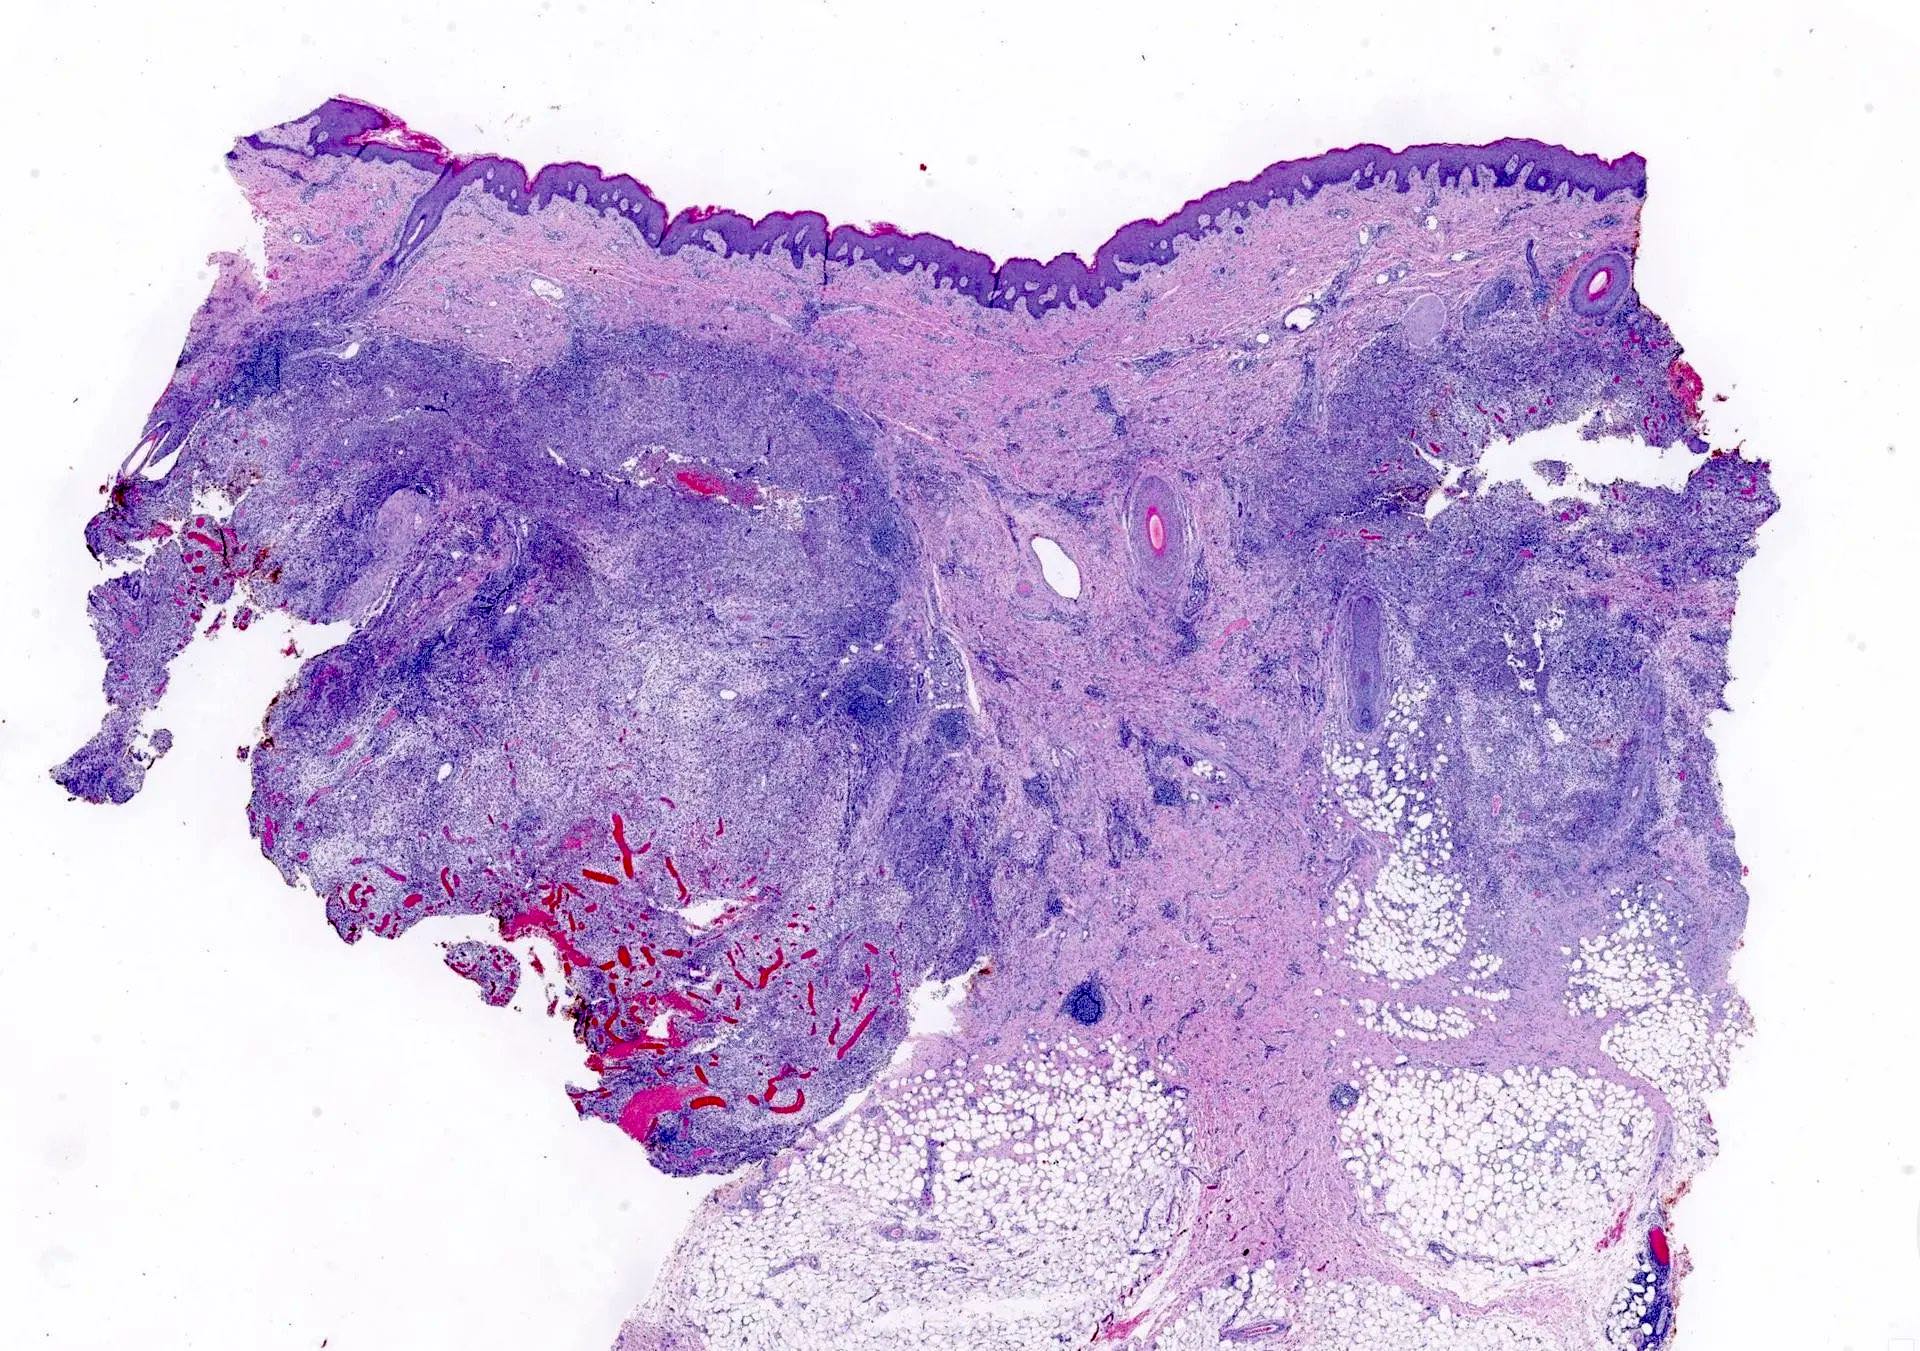

Microscopic (histologic) description

- In early lesions: follicular hyperkeratosis, hyperplasia of follicular epithelium and perifolliculitis (Br J Dermatol 2011;164:367)

- Dermal mixed inflammatory cell infiltrate, sometimes extending into the subcutis (Br J Dermatol 1990;122:763)

- Neutrophilic abscesses, which may connect with squamous epithelium lined cysts and sinus tracts that extend to the skin surface (Br J Dermatol 1990;122:763)

- Cysts and sinus tracts contain laminated keratin and occasional hair follicles (Br J Dermatol 1990;122:763)

- Granulation tissue with occasional foreign body giant cells present in ~25% of cases (Histopathology 1993;23:111)

- Inflammation involves apocrine glands in a minority of cases (J Am Acad Dermatol 1996;34:994)

- Dense fibrosis surrounding areas of follicular rupture

Microscopic (histologic) images